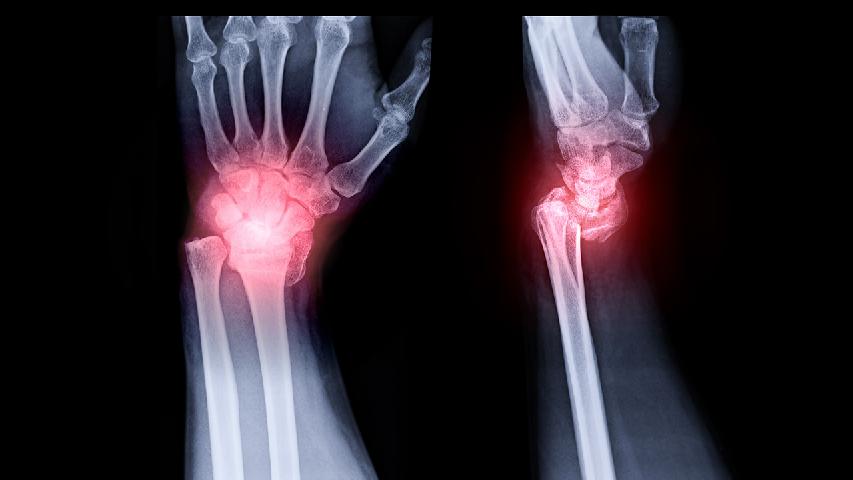

骨刺属中医的"痹证"范畴,亦称"骨痹"。中医认为本病与外伤、劳损、瘀血阻络、感受风寒湿邪、痰湿内阻、肝肾亏虚骨质增生病因等有关。大家对于骨刺的危害都比较了解,如果得了骨刺基本生活行为都会受到极大的影响。那么它是如何产生的?

1、病理学:不规则的软骨损害,在负重区域的软骨下骨硬化、囊肿,边缘骨赘增生,干骺端血流增加及不同程度的滑膜炎。

2、组织学:早期软骨表面碎裂、软骨细胞增生、软骨面纵向裂开、结晶沉积,同时存在着软骨修复、骨赘增生;晚期出现软骨的彻底破坏,表现为软骨硬化、软骨消失及软骨下局灶性骨坏死。

3、生物力学:关节软骨的可伸张性、抗压力、抗剪切力及软骨通透性降低。软骨水分增加,过度肿胀,软骨下骨硬化。